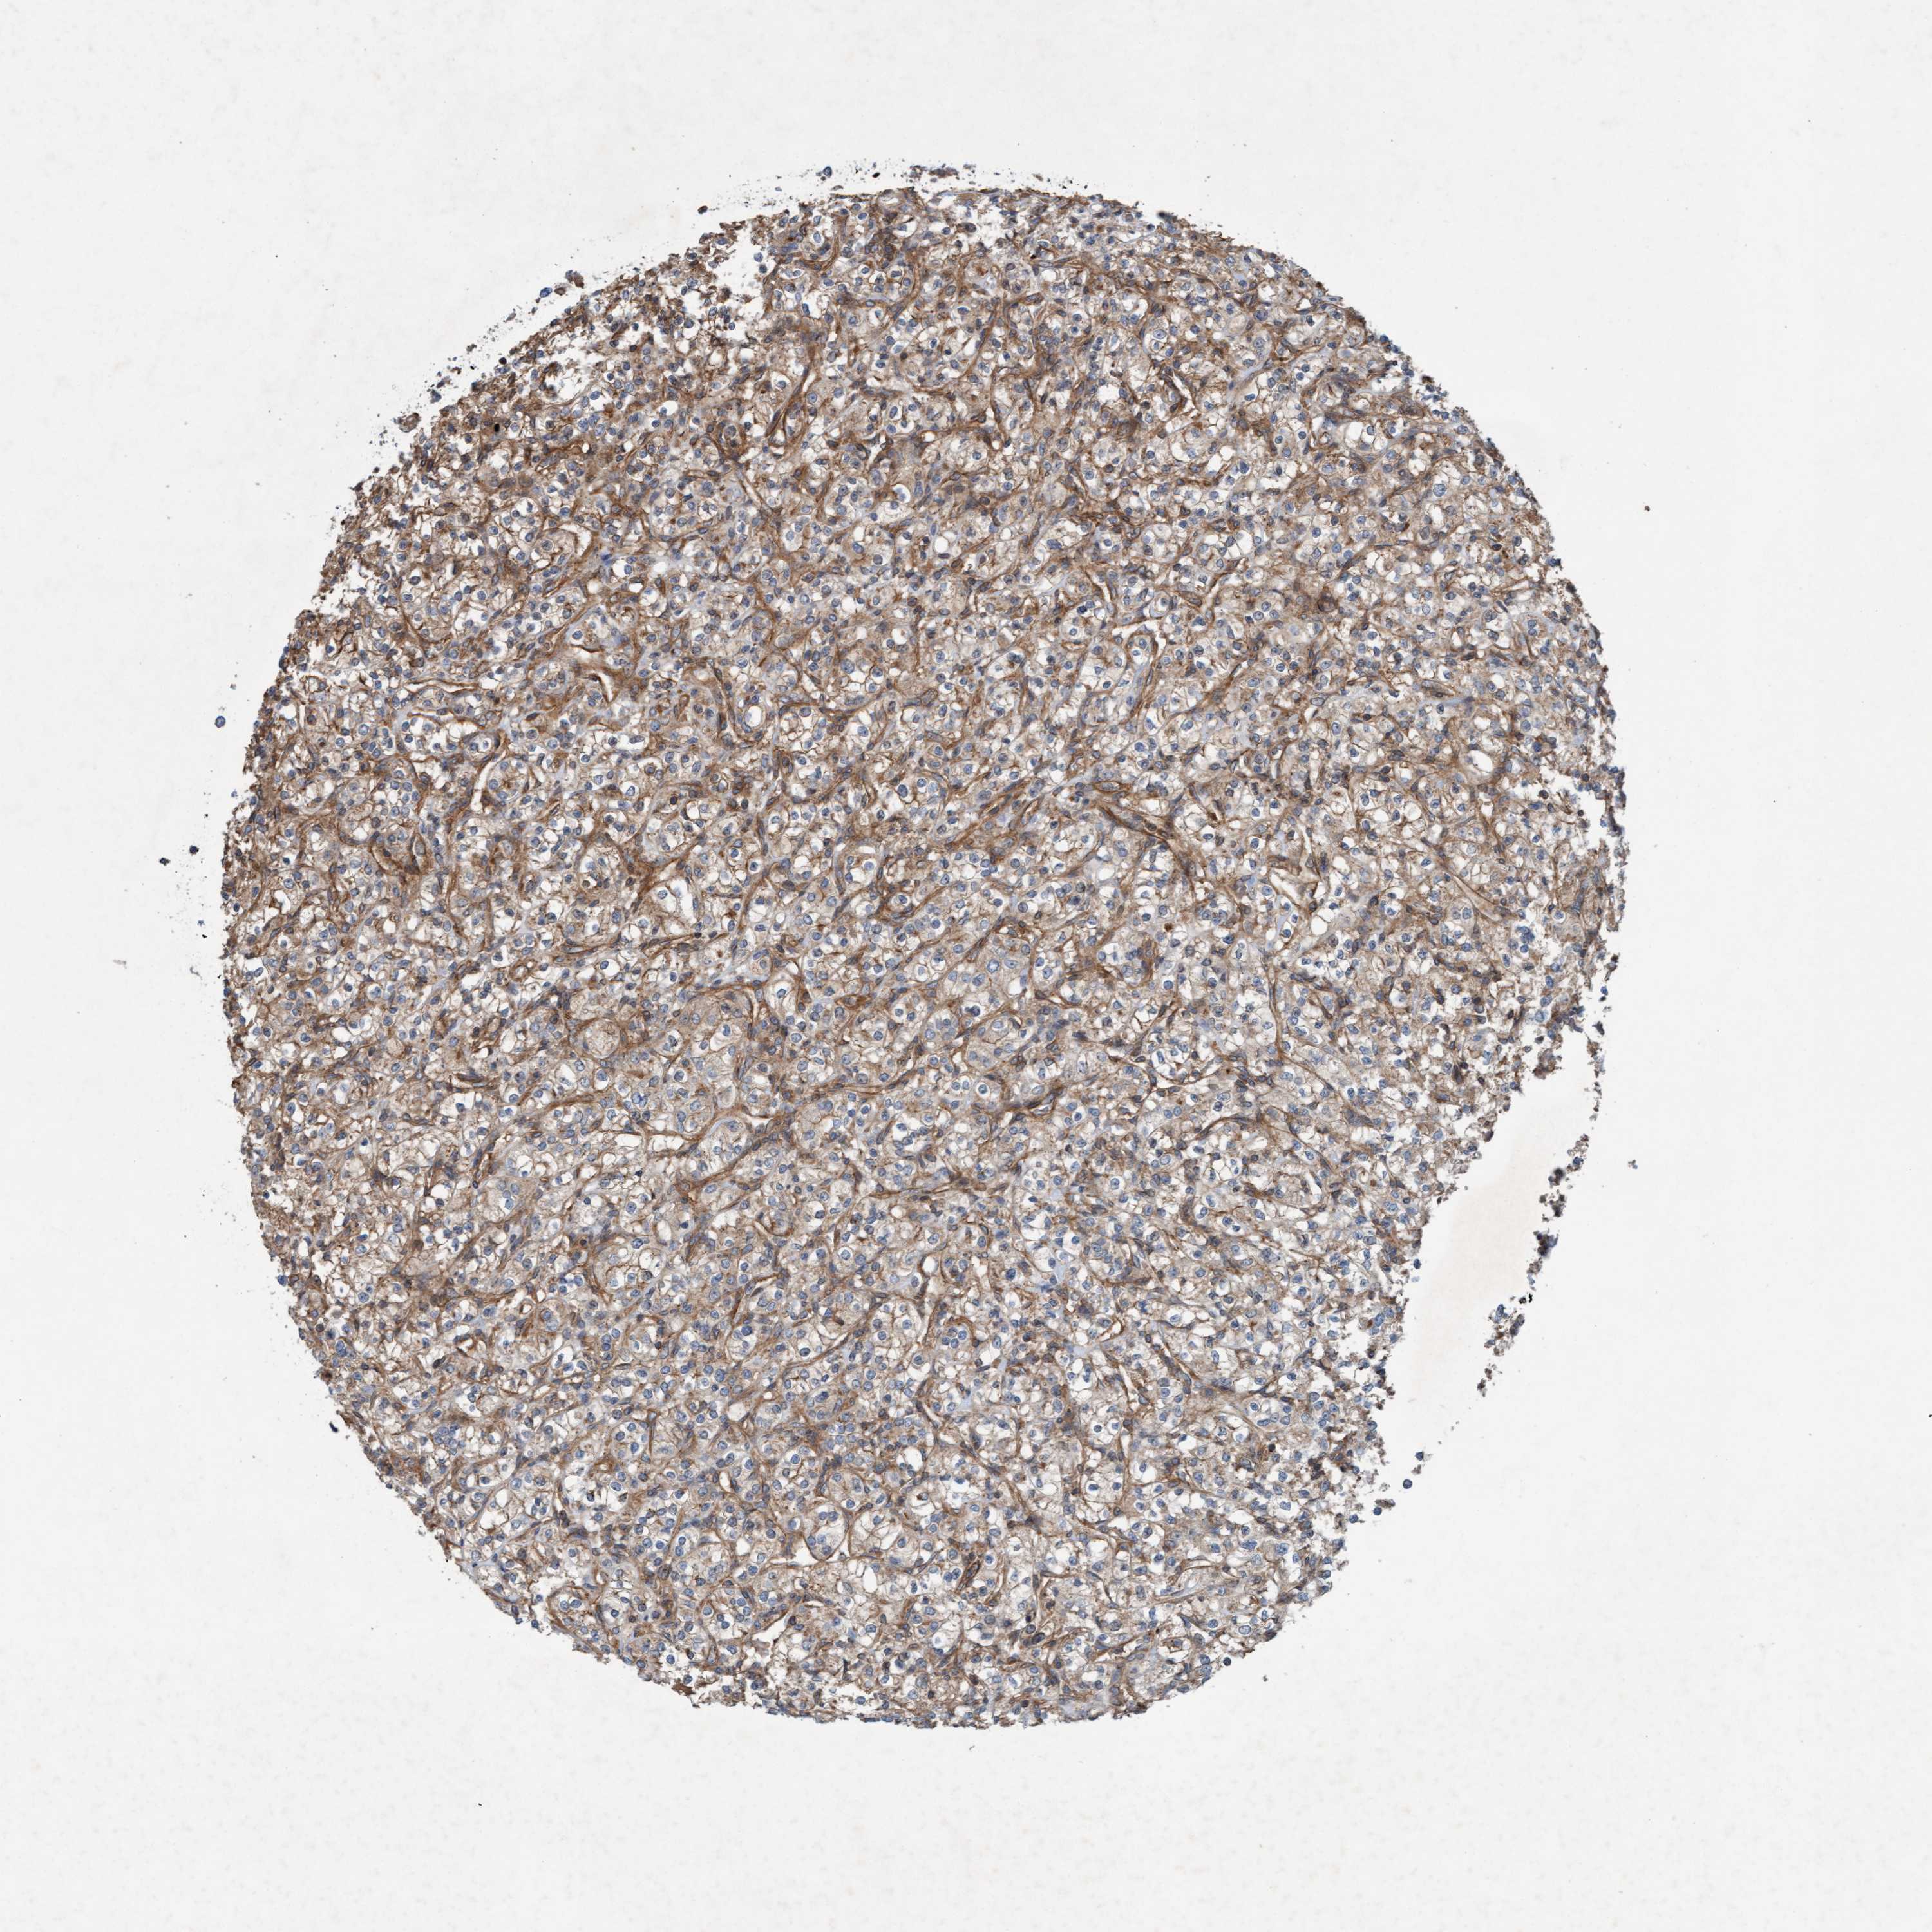

KIDNEY RENAL CLEAR CELL CARCINOMA (TCGA) - Interactive survival scatter ploti

The Survival Scatter plot shows the clinical status (i.e. dead or alive) for all individuals in the patient cohort, based on the same data that underlies the corresponding Kaplan-Meier plots. Patients that are alive at last time for follow-up are shown in blue and patients who have died during the study are shown in red.

The x-axis shows the expression levels (FPKM) of the investigated gene in the tumor tissue at the time of diagnosis. The y-axis shows the follow-up time after diagnosis (years). Both axes are complimented with kernel density curves demonstrating the data density over the axes. The top density plot shows the expression levels (FPKM) distribution among dead (red) and alive patients (blue). The right density plot shows the data density of the survived years of dead patients with high and low expression levels respectively, stratified using the cutoff indicated by the vertical dashed line through the Survival Scatter plot. This cutoff is automatically defined based on the FPKM cutoff that minimizes the p-score. The cutoff can be changed by dragging the vertical line or by entering a cutoff value in the square labeled "Current cut-off".

Under the Survival Scatter plot the p-score landscape (black curve; left axis) is shown together with dead median separation (red curve; right axis). Dead median separation is the difference in median mRNA expression between patients who have died with high and low expression, respectively. It is calculated as follows: median FPKM expression of dead patients with high expression - median FPKM expression of dead patients with low expression. This is intended to aid the user in visually exploring custom cutoffs and the associated p-scores and dead median separation.

Individual patient data is displayed and can be filtered by clicking on one or more of the category buttons on the top of the page. Categories describing expression level and patient information include: high, low, alive, dead, female, male and tumor stages. The scale of the x-axis can be toggled between linear and log-scale by clicking on the "x log" button. Mouse-over function shows TCGA ID, patient information and mRNA expression (FPKM) for each patient.

& Survival analysisi

Kaplan-Meier plots summarize results from analysis of correlation between mRNA expression level and patient survival. Patients were divided based on level of expression into one of the two groups "low" (under cut off) or "high" (over cut off). X-axis shows time for survival (years) and y-axis shows the probability of survival, where 1.0 corresponds to 100 percent.

ERAL1 is not prognostic in Kidney Renal Clear Cell Carcinoma (TCGA)

: 29.92

Average pTPM 33.0

Number of samples 521